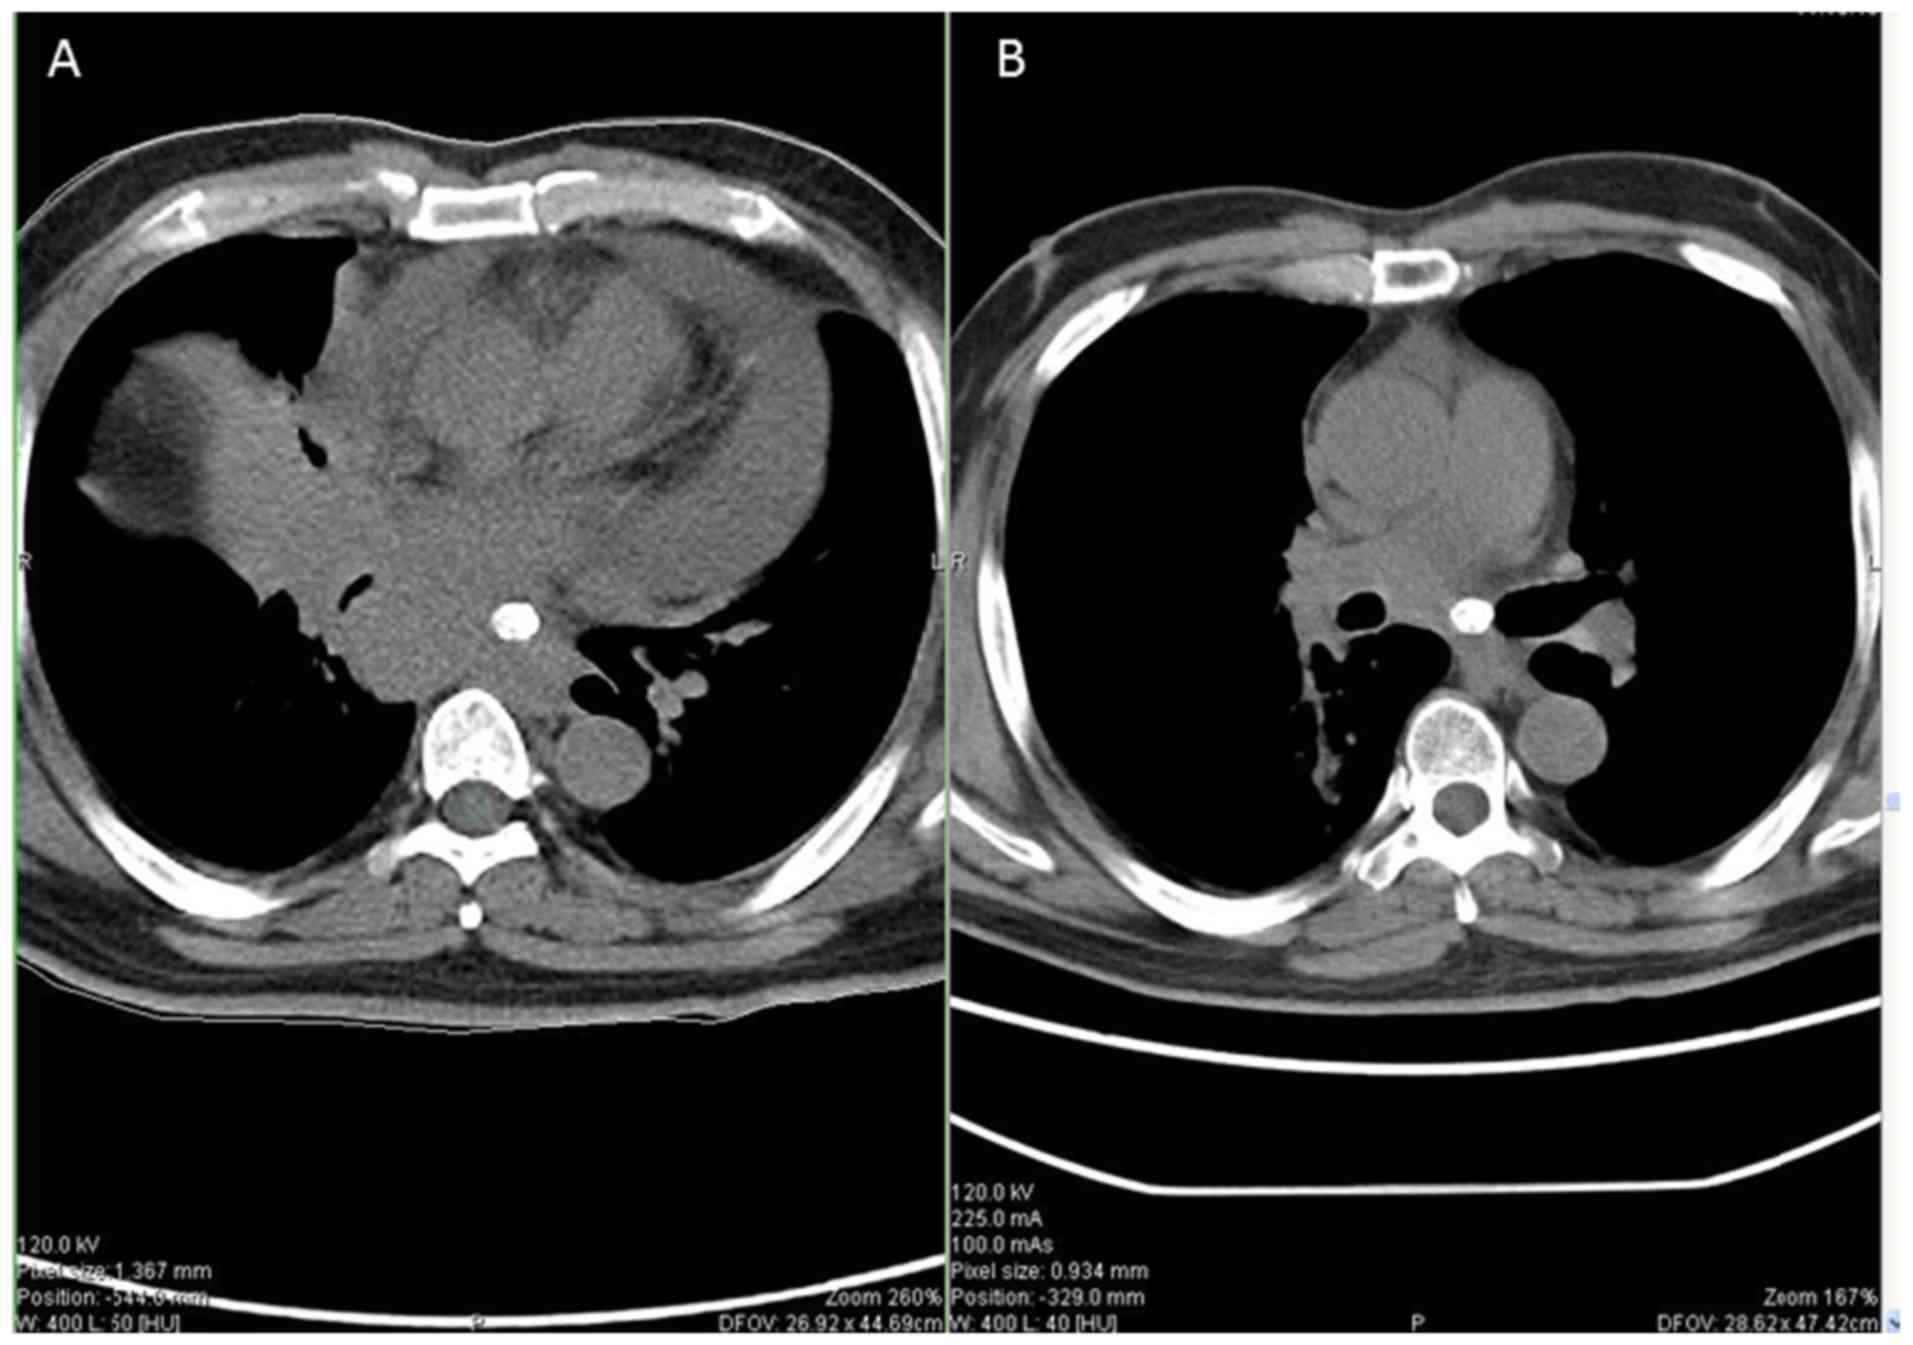

A 44-year-old male was diagnosed with extensive-stage small-cell lung cancer (ES-SCLC) accompanied by bone, brain and mediastinal lymph node metastasis. Between March, 2019 to August, 2019, he received systemic treatment with 6-cycle etoposide and cisplatin (EP) chemotherapy (etoposide 165 mg/m2 on days 1-3, and cisplatin 50 mg/m2 on days 1-2) followed by 200 mg pembrolizumab (Keytruda®, Merck Sharp & Dohme Corp.) intravenously once every 3 weeks, and the curative efficacy was evaluated as progressive disease (PD). He arose with facial paralysis, facial numbness, pain, tinnitus and limb joint pain on September 23, 2019 (Fig. 1A), although he had tendon reflexes. An enhanced cranial MRI examination revealed that there were abnormal enhancement areas in the left pontine crus, with clear boundaries (Fig. 2A). Facial nerve thickening and swelling caused facial paralysis. According to the toxicity grade, it was classified as grade 2. Thus, the use of pembrolizumab was terminated, although EP chemotherapy continued and he was treated with high-dose hormone therapy with the resolution of neurological symptoms. Methylprednisolone at 40 mg was administered for 5 days and he was then treated with oral prednisone tablets (25 mg). After 1 week, his facial symptoms were significantly alleviated (Fig. 1B). Following hormone therapy, the re-examination of the head MRI revealed that the lesion had shrunk and symptoms had improved (Fig. 2B). Subsequently, he was treated with etoposide/tenoposide alone, and he did not exhibit any signs of neurotoxicity. After completing the whole chemotherapeutic regimen, the primary tumor had markedly shrunk when comparing pre-treatment (Fig. 3A) and post-treatment (Fig. 3B).